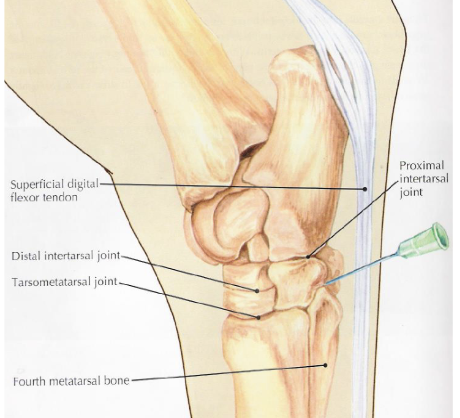

what are the bones of the tarsus

distal tibia, calcaneus + sustentaculum tali (fused), talus (+ medial and lateral trochlea), central tarsal bone, 3rd tarsal bone, 4th tarsal bone, fused 1 & 2 tarsal bone, proximal 2 3 and 4 metatarsal bones

joints of the tarsus

red- tibiotarsal (or tarsocrural)

green- proximal intertarsal

blue- distal intertarsal

purple- tarsometatarsal

which joints of the tarsus communicate w/ e/o

tibiotarsal and proximal intertarsal joints

which tarsal joints are the most common sites of arthritis in horses

distal intertarsal and tarsometatarsal

what is desensitized in a tarsometatarsal joint block

joint

what is desensitized in a distal intertarsal joint block

joint